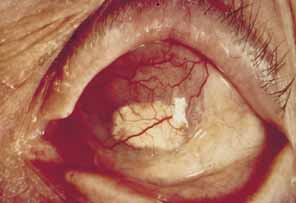

without ischemia, and causes a more diffuse iris atrophy.16,72,73  Fig. 16 Herpes zoster ophthalmicus. Corneal edema, abscess formation, and hypopyon

iridocyclitis in an eye that was subsequently enucleated for intractable

glaucoma and pain. Fig. 16 Herpes zoster ophthalmicus. Corneal edema, abscess formation, and hypopyon

iridocyclitis in an eye that was subsequently enucleated for intractable

glaucoma and pain.

|